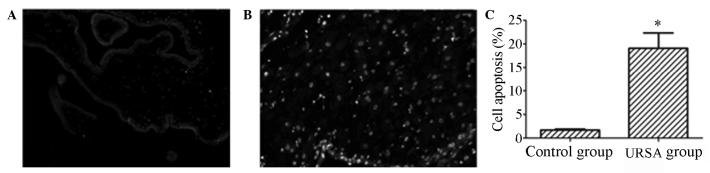

The aim of this study was to explore the level of apoptosis and p53 expression in the placental villi of patients with unexplained recurrent spontaneous abortion (URSA). Fifty-three pregnant females with URSA and 32 pregnant females who required an induced abortion were selected as the subjects of this study. Placental villus tissues were collected from June 2010 to June 2012 and quantitative polymerase chain reaction (qPCR) and immunohistochemical analysis were performed to determine the mRNA and protein levels of p53 in the placental villus tissues. The level of apoptosis in the tissues was studied using terminal deoxynucleotidyltransferase-mediated dUTP nick end labeling (TUNEL) assay. The mRNA and protein expression levels of p53 in the URSA group were significantly higher than those in the control group (P<0.05). Furthermore, the levels of apoptosis were increased markedly in the URSA group compared with the control group (P<0.05). In conclusion, the placental villi of patients with URSA express a high level of p53, which may result in cell apoptosis and lead to recurrent spontaneous abortion.

本研究旨在探讨原因不明的复发性自然流产(URSA)患者胎盘绒毛中的细胞凋亡水平及p53表达情况。选取53例URSA孕妇和32例需要人工流产的孕妇作为本研究对象。于2010年6月至2012年6月采集胎盘绒毛组织,采用定量聚合酶链反应(qPCR)和免疫组织化学分析方法测定胎盘绒毛组织中p53的mRNA和蛋白水平。采用末端脱氧核苷酸转移酶介导的dUTP缺口末端标记法(TUNEL)检测组织中的细胞凋亡水平。URSA组中p53的mRNA和蛋白表达水平显著高于对照组(P<0.05)。此外,与对照组相比,URSA组的细胞凋亡水平明显升高(P<0.05)。综上所述,URSA患者的胎盘绒毛表达高水平的p53,这可能导致细胞凋亡并引发复发性自然流产。